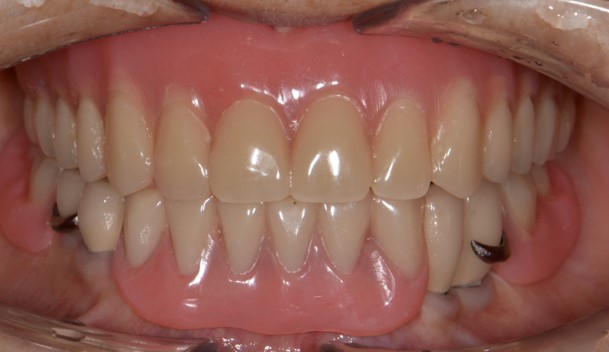

상악 완전틀니, 하악 임플란트 크라운 지지 부분 틀니

After